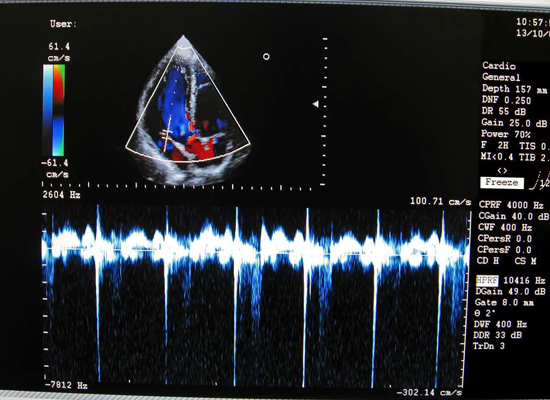

Contamos con equipos de ultrasonido de alto desempeño y resolución de imagen. Con capacidad de realizar estudios de 4 D y elastografia, realizamos todos los estudios de ultrasonido como son:

• Doppler y vascular periférico

La elastografia tal cual su nombre lo indica es una técnica ultrasonigrafica en codificación de colores los cuales van a variar de acuerdo a la elasticidad específica de los tejidos. Una característica de posibles lesiones malignas es la pérdida de esta elasticidad de tal forma el doctor al realizar el estudio al notar esta pérdida de elasticidad ayuda significativamente a su diagnóstico.